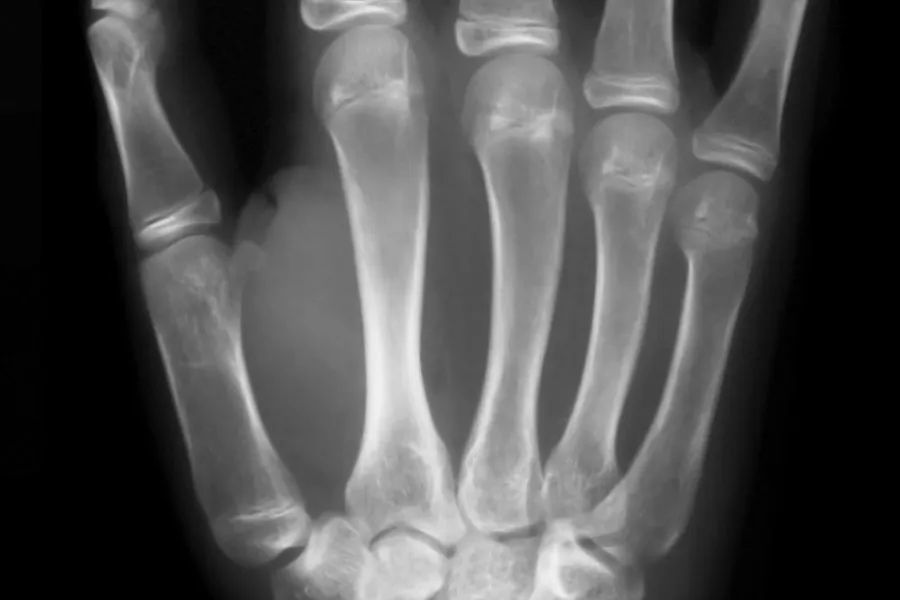

Begrepet biologisk aldersvurdering brukes der en benytter seg av biologiske metoder og parametere for å forsøke å fastsette alderen til et individ. Metodene vil være objektive sammenlignet med for eksempel et intervju eller en uttalelse fra en pårørende, og brukes sammen med andre opplysninger for å gjøre en helhetlig vurdering av alder.